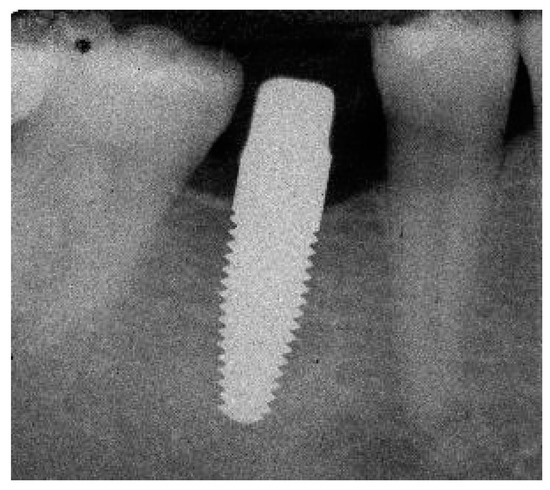

Radiograph of the perimplant bone situation before crown cementation.

Figure A15.

Figure A18.

Radiograph of the perimplant bone situation at the 1-year follow-up. The bone loss is already advanced. Therapy: conventional subgingival cleaning with ultrasound and plastic tips; rinsing with chlorhexidine, reinforcement personal oral hygiene.